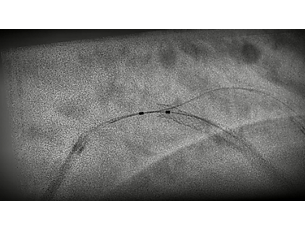

Our imaging technology ClarityIQ, combines advanced, real-time image noise reduction algorithms with state-of-the-art hardware. Together, they form a flexible digital imaging pipeline designed to perform individual image processing algorithms more efficiently. This unlocks superb visualization and significant dose reduction capabilities for healthcare facilities. ClarityIQ is available as an option on Azurion systems.

StentBoost Live

Dynamic Coronary Roadmap